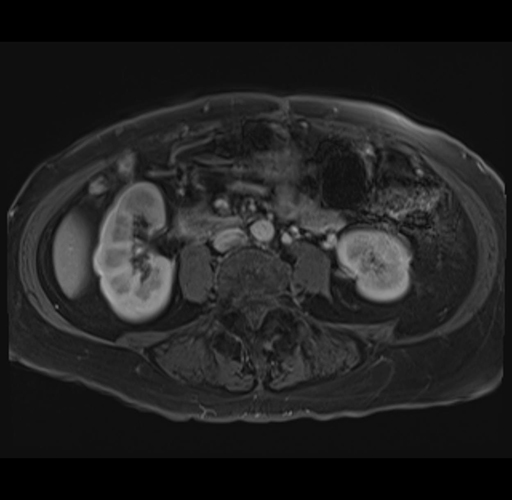

MRI T1